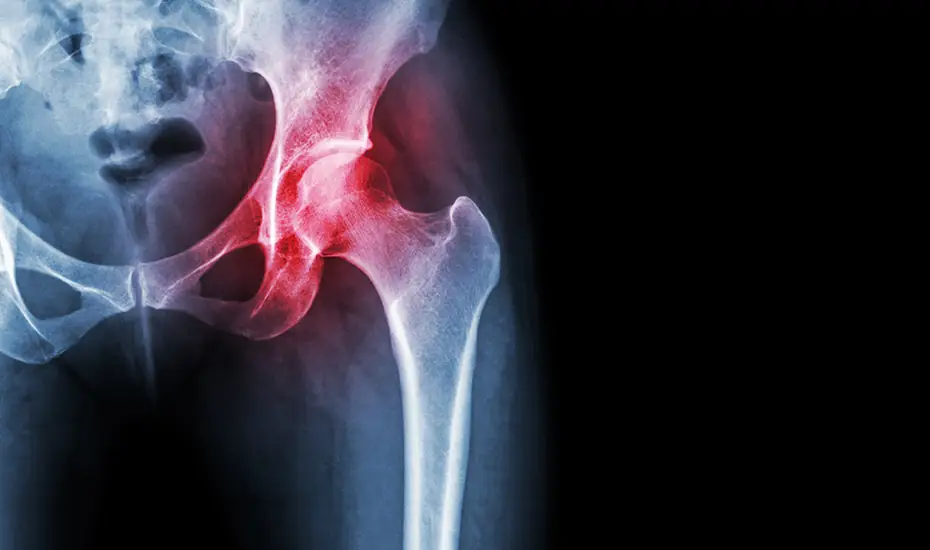

Sindromul piriform este o afectiune neuromusculara care apare atunci cand muschiul piriformis este iritat, inflamat sau are spasme musculare care aplica campresie pe nervul sciatic. Afectiunea provoaca adesea simptome similare cu sciatica. Piriformis este un muschi mic situat adanc in fesa, in spatele gluteus maximus. Se ruleaza in diagonala, de la nivelul coloanei vertebrale inferioare la suprafata superioara a femurului, cu rularea nervului sciatic dedesubt sau prin muschi.

Acest muschi permite mersul normal, trecerea greutatii corporale de pe un picior pe altul si mentinerea echilibrului. De asemenea, este folosit in cadrul activitatilor sportive care presupun ridicarea si rotirea coapselor, pe scurt – in aproape fiecare miscare. Nervul sciatic este un nerv lung care trece de-a lungul muschiului piriformis spre partea inferioara a membrului pelvin si se ramifica in regiunea poplitee, asigurand inervatia musculaturii si a pielii (tegumentelor) membrului inferior. Compresia nervului sciatic poate fi cauzata de spasmele muschiului piriform.

Sindromul piriform debuteaza cu dureri, senzatie de furnicaturi si amorteala in zona feselor. Durerea poate fi severa si se poate extinde de-a lungul nervului sciatic. Senzatia de durere este cauzata de comprimarea nervului sciatic de catre muschiul piriform, cand o persoana sta in anumite pozitii timp indelungat (cum ar fi stand pe scaun) sau cand alearga. Durerea poate fi declansata inclusiv de urcatul scarilor, cand se aplica o presiune ferma, directa asupra musculaturii piriforme. Cu toate acestea, cele mai multe cazuri de sciatica nu sunt declansate de sindromul piriform.